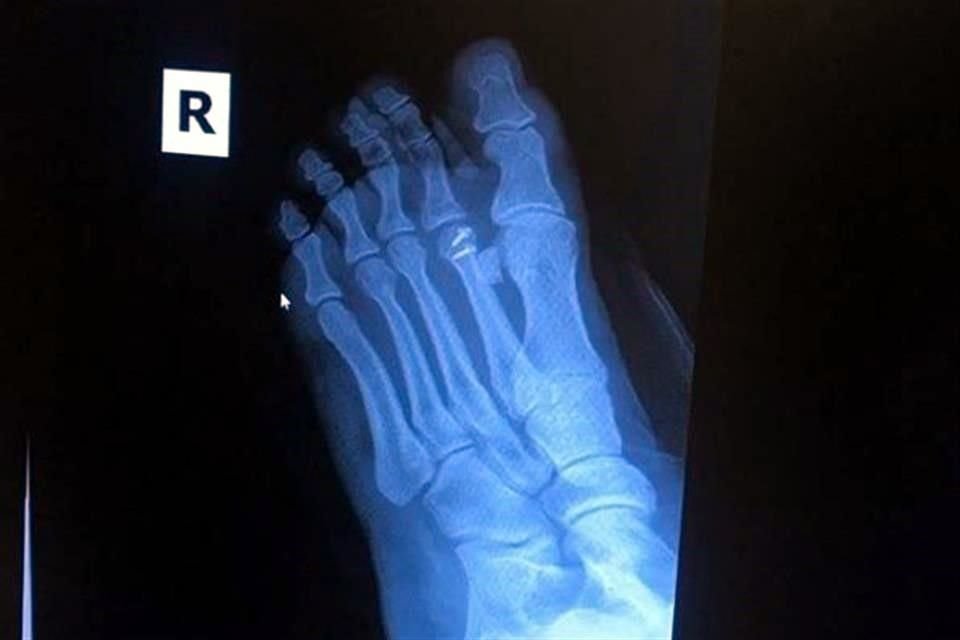

Un auto le causó una fractura a la actriz Laura Flores. Crédito: tomada de Instagram @laurafloresmx

Le tuvieron que ser colocados dos clavos en el pie para reconstruirlos. Crédito: tomada de Instagram @laurafloresmx

Con la reconstrucción de un dedo del pie resultó Laura Flores, quien tuvo un accidente cuando se transportaba en bicicleta.